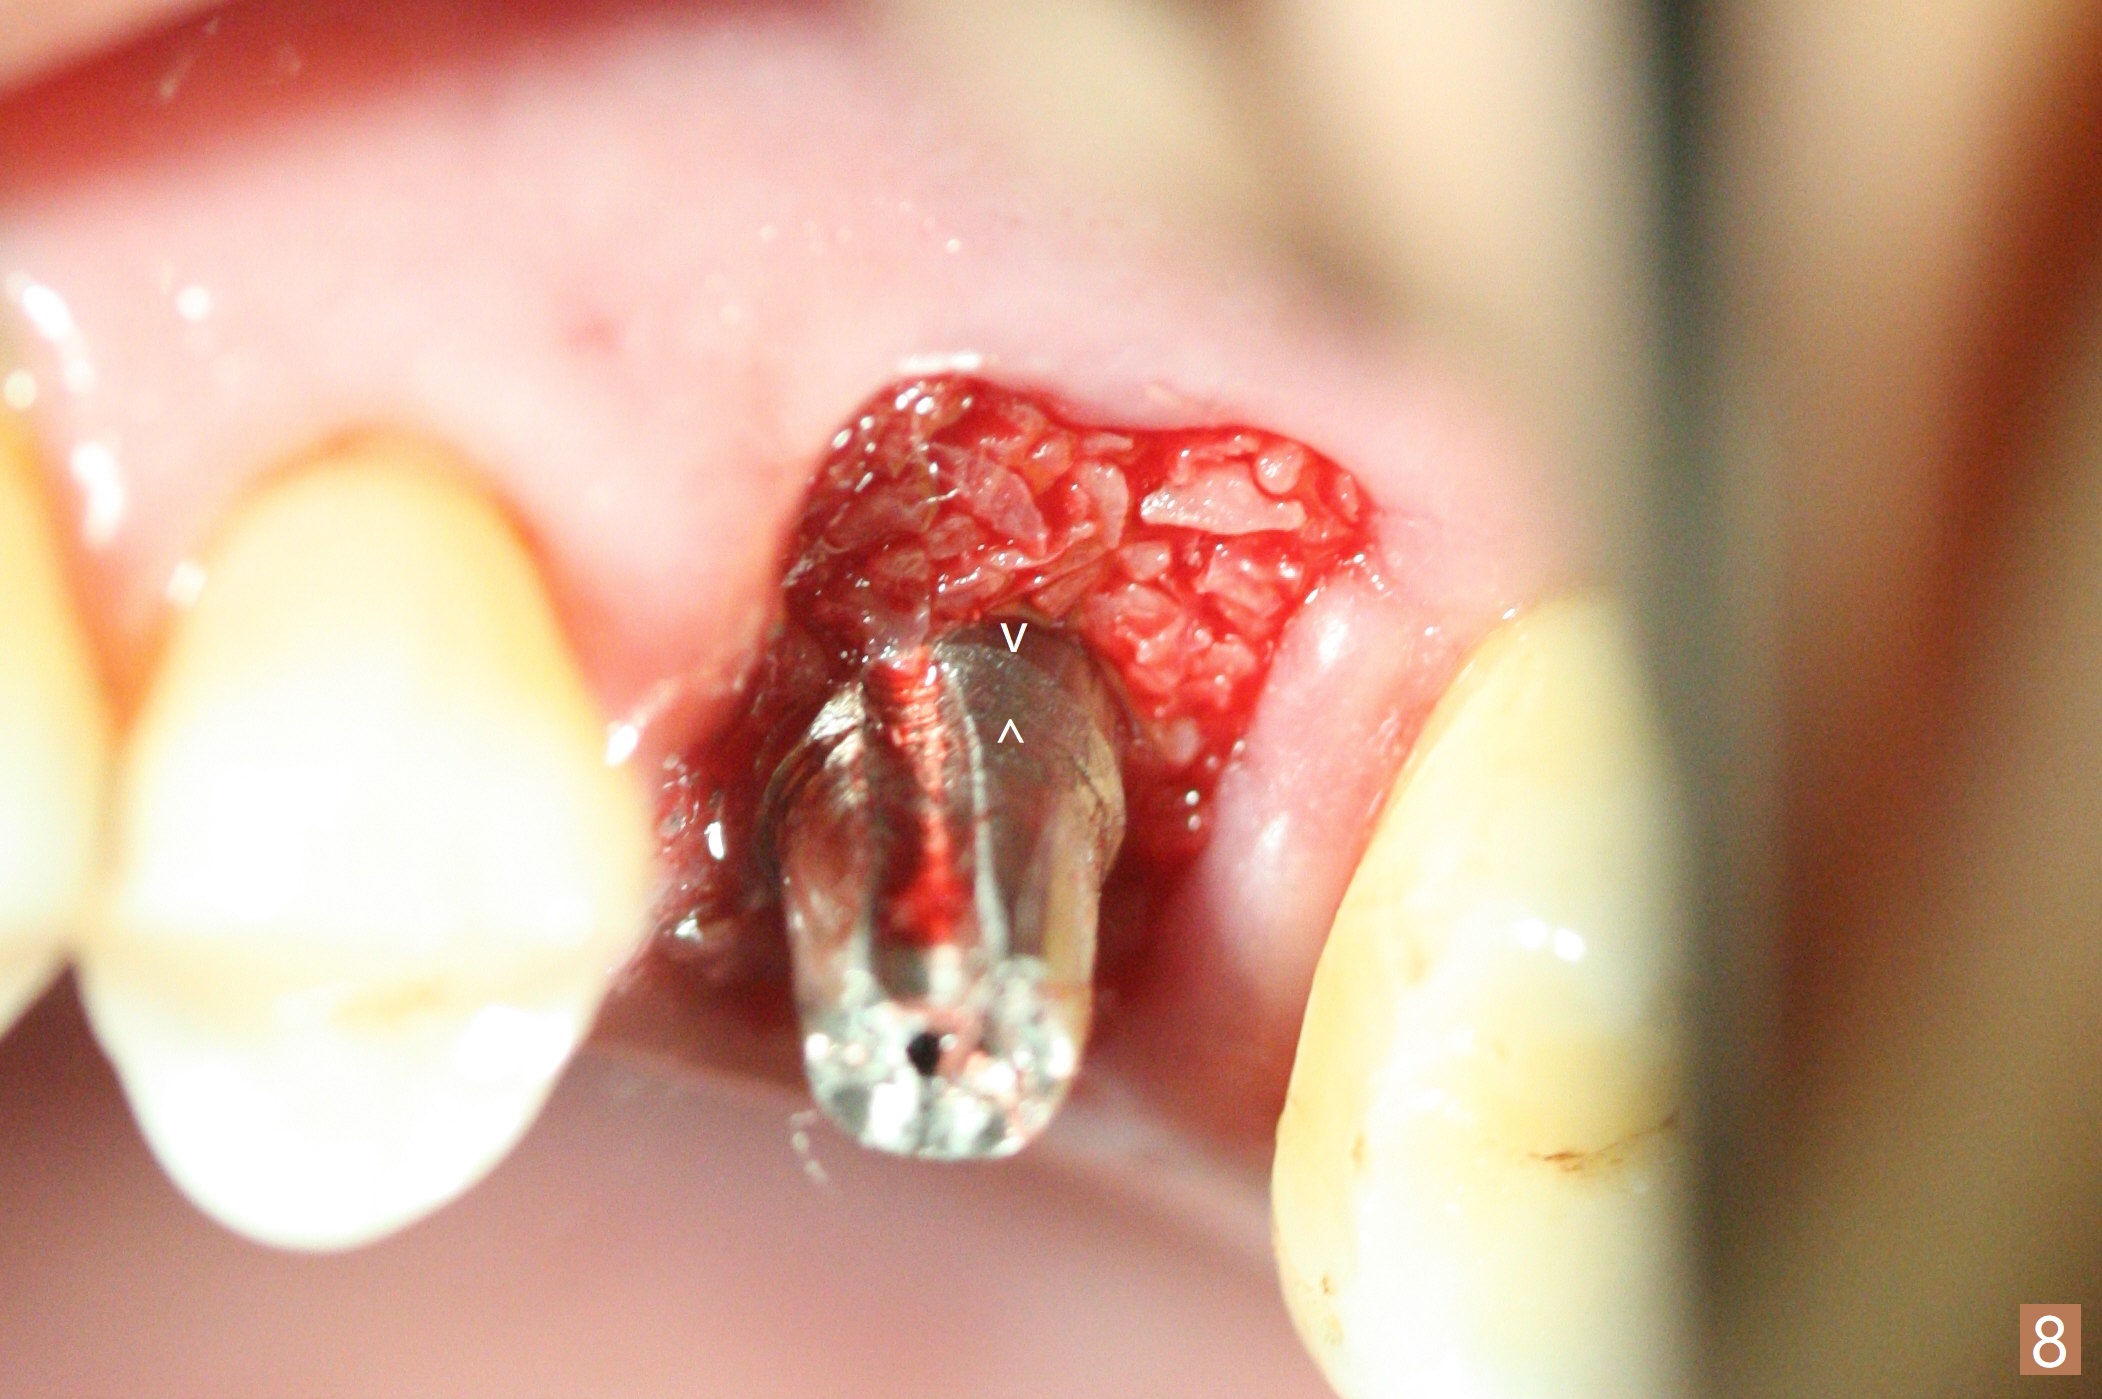

A 65-year-old man had crack tooth syndrome at #14 one month earlier (Fig.1). He shows up with crack and pain in an emergency manner (Fig.2 arrowheads). Preop CT confirms 4.5 mm bone height (Fig.3). Osteotomy will be initiated in the middle of the septum between 3 sockets (Fig.4). Depth of osteotomy is controlled with drill stoppers. After sequential osteotomy free hand, a 5x11 mm tap is used to break through the sinus floor (Fig.5) and sinus lift with Vanilla allograft. To prevent abutment screw loosening, a 5x11 mm tissue-level implant is placed; the distal thread is equicrestal (Fig.6 arrowhead). Following deeper placement of the implant (Fig.7 arrow) with a larger and longer abutment (as compared to that in Fig.6), the margin for an immediate provisional (Fig.9 white curved lines) is prepared in the coronal end of the implant (Fig.8 between arrowheads). With the tissue-level implant, the crown/implant ratio improves. Stress will be partially acting on the implant so that there is less likelihood of abutment screw loosening. The socket heals 1 month postop (Fig.10). The rough surface of the implant is exposed ~ 1 mm. With the margin modified and polished, the provisional returns to place with oral hygiene instruction. It is hoped that the gingiva will cover the exposed rough surface. The buccal rough surface remains exposed 5 months postop (Fig.11). The bone in sinus lift is mature 5 months postop (Fig.12,13). The first 1-2 implant threads are expected to be filled with mature bone in the near future (*). Since the abutment seems long enough for retention, temp bond is used for cementation (Fig.14). Water pik is being applied.